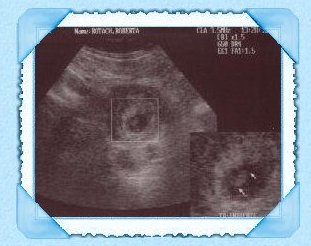

Our first ultrasound of our baby.

There is a BABY in there giggle!

The second ultrasound we have had.

This is so neato our baby has legs i can see.. giggle.

As you can tell I marked the ultrasounds so you can tell :)

Due to a lot of stress when Lonelywolf left to fight for our country our

baby was not moving and it had me worried.

I went to the doctor and they did another ultrasond on me.

This is when i got the wav of the babies heart beat so Wolf could hear.

IT'S A BOY!!!!!